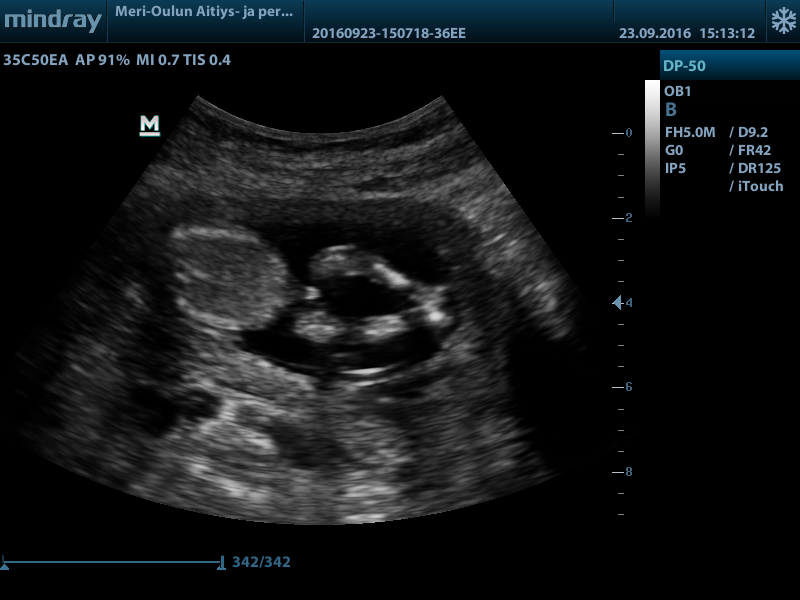

Hi! Would love your thoughts regarding the gender. Boy or girl? (And maybe why, I'm really new at this.. )

Top of the baby isn't the best for nub guessing but at 13 weeks girl parts wouldn't be so...large... At that gestation. I'm a few of the pictures I am almost positive I see testicles too so my guess is boy :) will actually be a little shocked if you hear girl please update when you know!